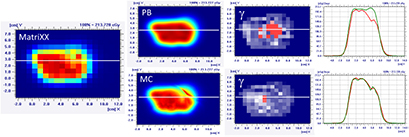

Standard image High-resolution imageThe MatriXX measurement of the configuration represented in figure 4, confirmed what was expected from the MC recalculation: the PB dose profile was higher compared to the measurements and the γ passing rate of the dose distribution estimated on the MatriXX was 57.6%. The MC recalculation is much closer to the experimental data and had a gamma passing rate of 97.8% (see figure 5 and table 1).

Figure 5. Dose distribution and γ analysis comparison between the MatriXX measurement and the PB or MC dose engine in a transversal plane for the 1/6 head phantom with a gantry angle of 70° and snout position of 42 cm. The white lines represent the dose profiles' extraction plans, the red lines are the measured data profile while the green lines represent the calculated dose distribution. The red region in the γ graph represents the area with γ > 1.

Figure 7. Dose distribution and γ analysis comparison between the MatriXX measurement and the PB or MC dose engine in a transversal plane for the 2/6 head phantom with a gantry angle of 70° and a snout position at 42 cm. The white lines represent the dose profiles' extraction plans, the red lines are the measured data profile while the green lines represent the calculated dose distribution. The red region in the γ graph represents the area with γ > 1.

Download figure: